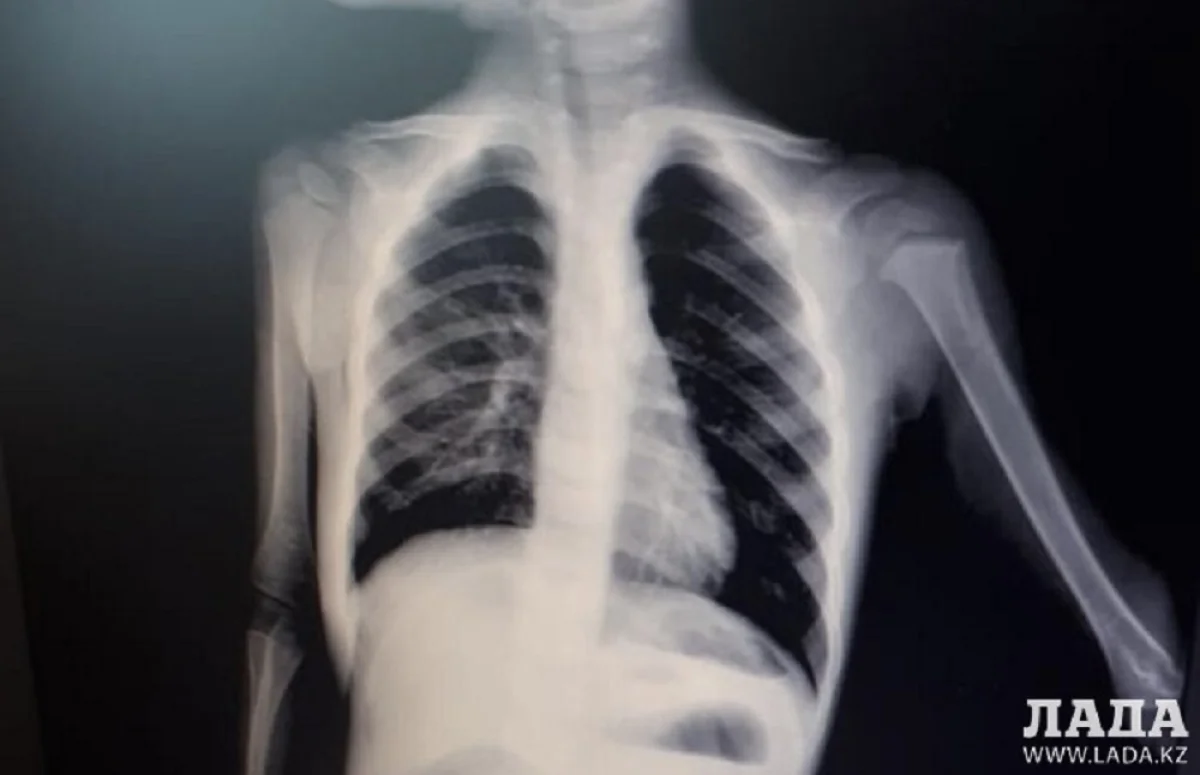

Ребенка, проглотившего соску, из Жанаозена доставили в Мангистаускую детскую больницу. Инородный предмет извлечен. Состояние удовлетворительное. Об этом сообщили в управлении здравоохранения Мангистау.

Ребенка доставили в медучреждение с болями в животе, рвотой и высокой температурой. В ходе обследования медики выявили наличие инородного предмета в желудке.

- Можно сказать, что изначально состояние ребенка было тяжелым, потому что у него была бесконечная рвота, мальчик был бледным и совсем ослаб. Самое главное - операция прошла успешно. В настоящее время двухлетний пациент чувствует себя хорошо. На моей практике за 21 год работы в медицине такое встречается впервые. Да, у нас были случаи, когда ребенок проглатывал монету, инородные предметы, но чтобы соску, такого я раньше не встречал, - рассказал Курман Кайранов, детский хирург высшей категории.